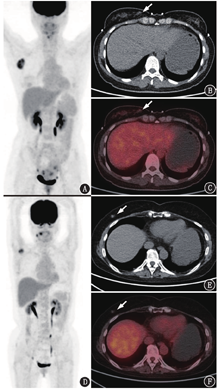

实际上对于乳腺结节的性质鉴别,18F-FDG PET/CT的诊断效能仍比较有限,以往研究认为18F-FDG PET/CT对乳腺癌的诊断灵敏度为48%~86%[11]。一方面,乳腺的其他感染或非感染性炎性疾病可以代谢增高,如各种乳腺炎、乳腺脓肿(图3)、结核感染等,影像学上与乳腺癌可能不易鉴别;另一方面,并非所有的乳腺癌都有高代谢的特征,其代谢程度主要与病理及分子特征相关,分化较好、导管原位癌及浸润性小叶癌的代谢通常偏低,而雌激素受体(estrogen receptor, ER;-)、孕激素受体(progesterone receptor, PR;-)、人表皮生长因子受体2(human epidermal growth factor receptor 2, HER2;+)、三阴性乳腺癌、细胞增殖核抗原Ki-67高、分化差、肿瘤体积大则与代谢较高相关[11,12,13]。此外,PET/CT上的隐匿性乳腺癌并不少见(图4),有时在转移灶明确的情况下,乳腺原发病灶可能代谢完全正常。